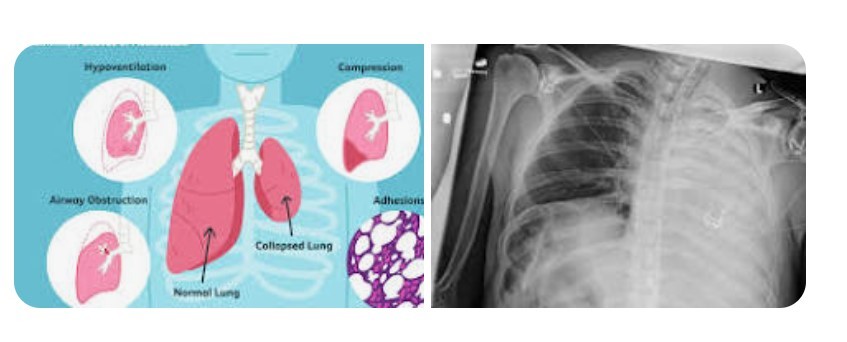

Respiratory system

-Assess full respiratory cycle

for observing chest wall and symmetry

We want open lungs and get air through

-Controlled coughing

3 deep breathes then forced cough

Patients with reduced mobility are at risk for retained pulmonary secretions, and this risk increases in postoperative patients. As a result of retained secretions, the respiratory rate increases.

The heart rate also increases because the heart is trying to improve oxygen levels.

These symptoms are of concern for older adults because, if left untreated, further complications such as heart failure can occur.